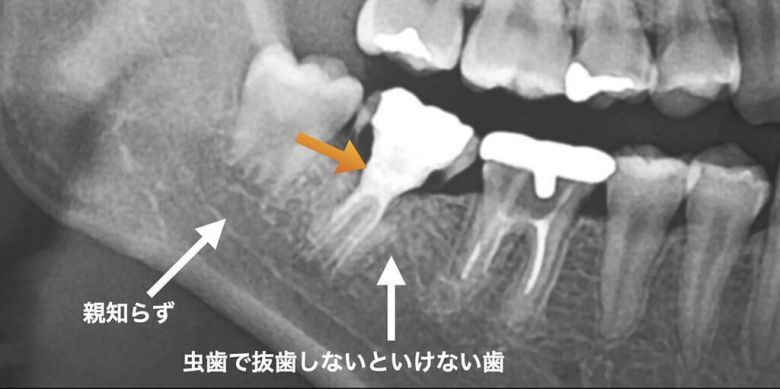

例えば一本抜かないといけない歯があって、その奥に親知らずが埋まっているという場合、親知らずを移植するという方法があります。移植の適応は限られていますが、もし、可能であればインプラントよりも自然に治癒するため、術後は快適に使用できます。ちなみに若年者ほど、成功率は高くなると言われています。

術前の状態